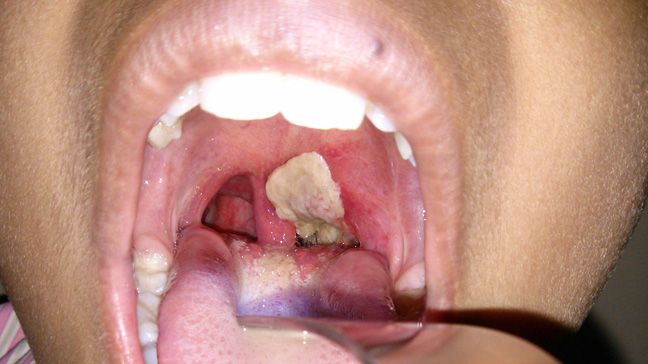

Presenting the motion under urgent public importance, Rotimi revealed that there was an outbreak of diphtheria at the boarding house of King’s College, Victoria Island Annexe, Lagos State.

He said, “A federal government-owned institution has been affected, leading to the tragic death of a 12-year-old student and the hospitalization of several others.